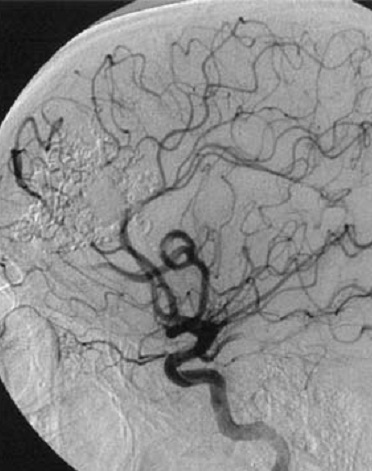

лизация мальформации

Эмболизация мальформации 113 фотографий